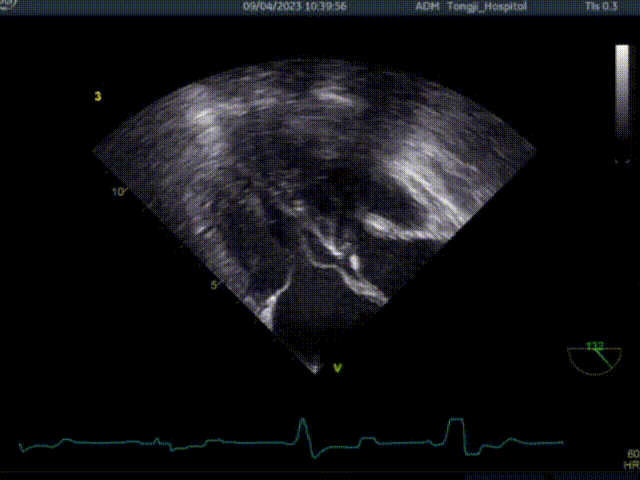

术前超声TEE检查结论:

1. 左室非对称性肥厚,左室流出道梗阻,二尖瓣重度关团不全;

2. 二尖期后叶脱垂;

患者术前大量反流,前叶SAM征,室间隔增厚最厚处13mm

共切除3刀